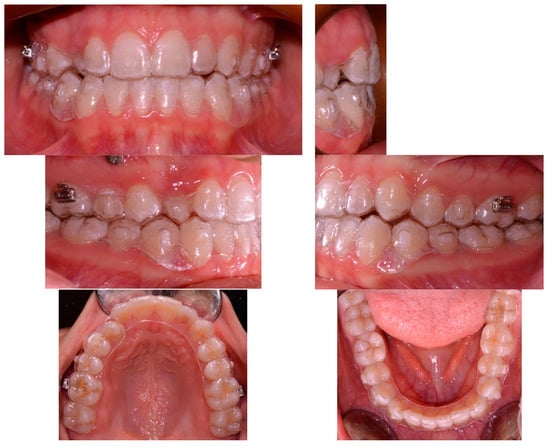

2.1. Clinical Case